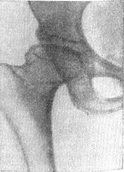

![]() Рис. 2. Хвороба Пертеса, III стадія, той же Сольною, що і на рис. 1, через 1 рік і 4 місяці. Нерівномірне розрідження деформованого і ущільненого епіфіза головки лівої стегнової кістки - картина секвестроподобных тіней, потовщення голівки та шийки стегнової кістки, розширення рентгенівської суглобової щілини, підвивих стегнової кістки назовні. |

Відповідно зміненій формі головки стегнової кістки змінюється і форма кульшової западини. Намічаються ознаки підвивиху стегнової кістки назовні (рис. 2). У цій стадії може виявитися нерізко виражений остеопороз. Тривалість її приблизно до двох років.